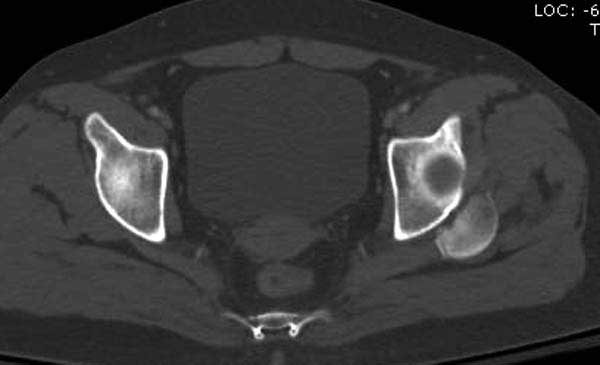

В диагноз еще необходимо внести закрытую (?) ротационно-нестабильную травму таза с переломами лонных седалищных костей, боковой массы крестца справа.

Перелом позвоночника и боковую компрессию таза отнесли к стабильным переломам и не стали форсировать события до лучших времен...

После спадения отека на стопе произведена фиксация тарана. Кстати, коллеги пересмотрели первоначальную консультацию по позвоночнику и на двух уровнях провели фиксацию. Из-за длительного постельного режима без нагрузки таз не стали оперировать...